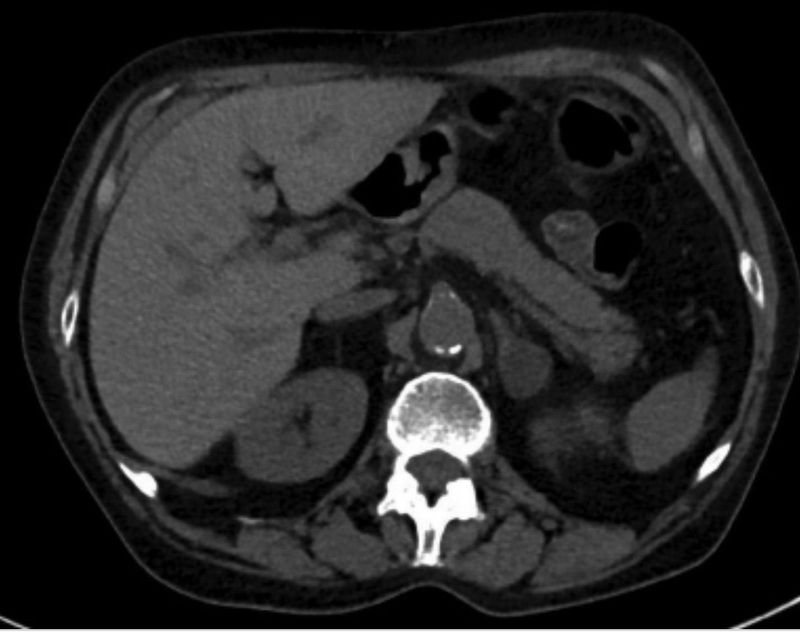

What do you see

Ok, it’s a bit hard, focus on retroperitoneal region mignopion😊

Look to opposite side 😉

that break in continuity of the wall behind kidney? ...though there also seems some calcification in aorta

We don’t operate patients for aort calcification, so what’s happening here😊?

doc suspense is killin me ....is it aortic dissection ?

Noo

Intraperitoneal hemorrhage, mostly on the right side.